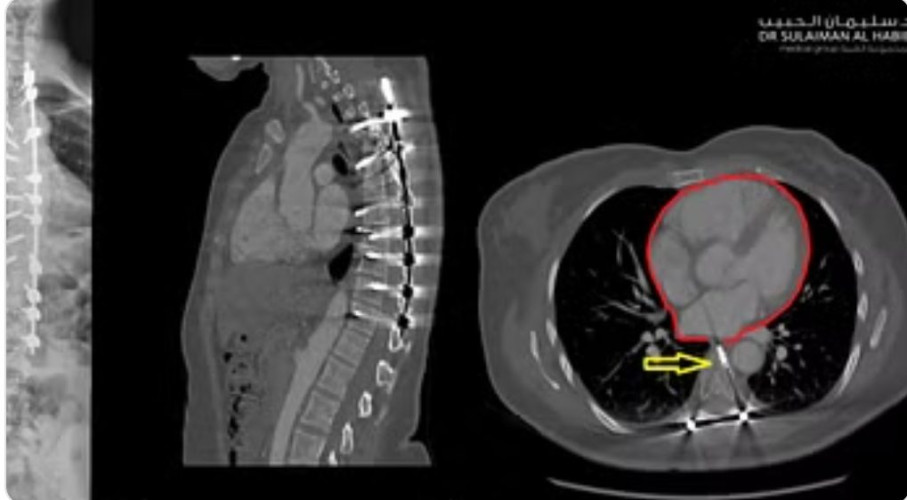

وأفاد بأن النتائج كشفت عن استخدام مسامير لتثبيت الفقرات ذات أطوال غير مناسبة في العملية السابقة، ووجود أقرب مسمار على بُعد 0.7 سم كاد يخترق الشريان الأورطي القلبي ويتسبب في الوفاة لا سمح الله؛ وهو المتسبب في شعورها بالأعراض السابق ذكرها؛ فضلًا عن اكتشاف تجمع للسوائل بالرئة.

وقال الدكتور السبيعي إنه بعد دراسة الفريق الطبي المعالج لكل النتائج؛ اتخذ القرار بالتدخل العاجل لإنقاذ المريضة؛ حيث تمت إزالة المسامير القريبة من الشريان الأورطي، وتغييرها بأخرى مناسبه لحجم الفقرات، دون تعريض المريضة لأية أذى، مع التأكد من عدم قربها من الأعصاب والحبل الشوكي، تَبِع ذلك تثبيت الفقرات وإجراء قص عظمي للعمود الفقري لتعديل التحدب.